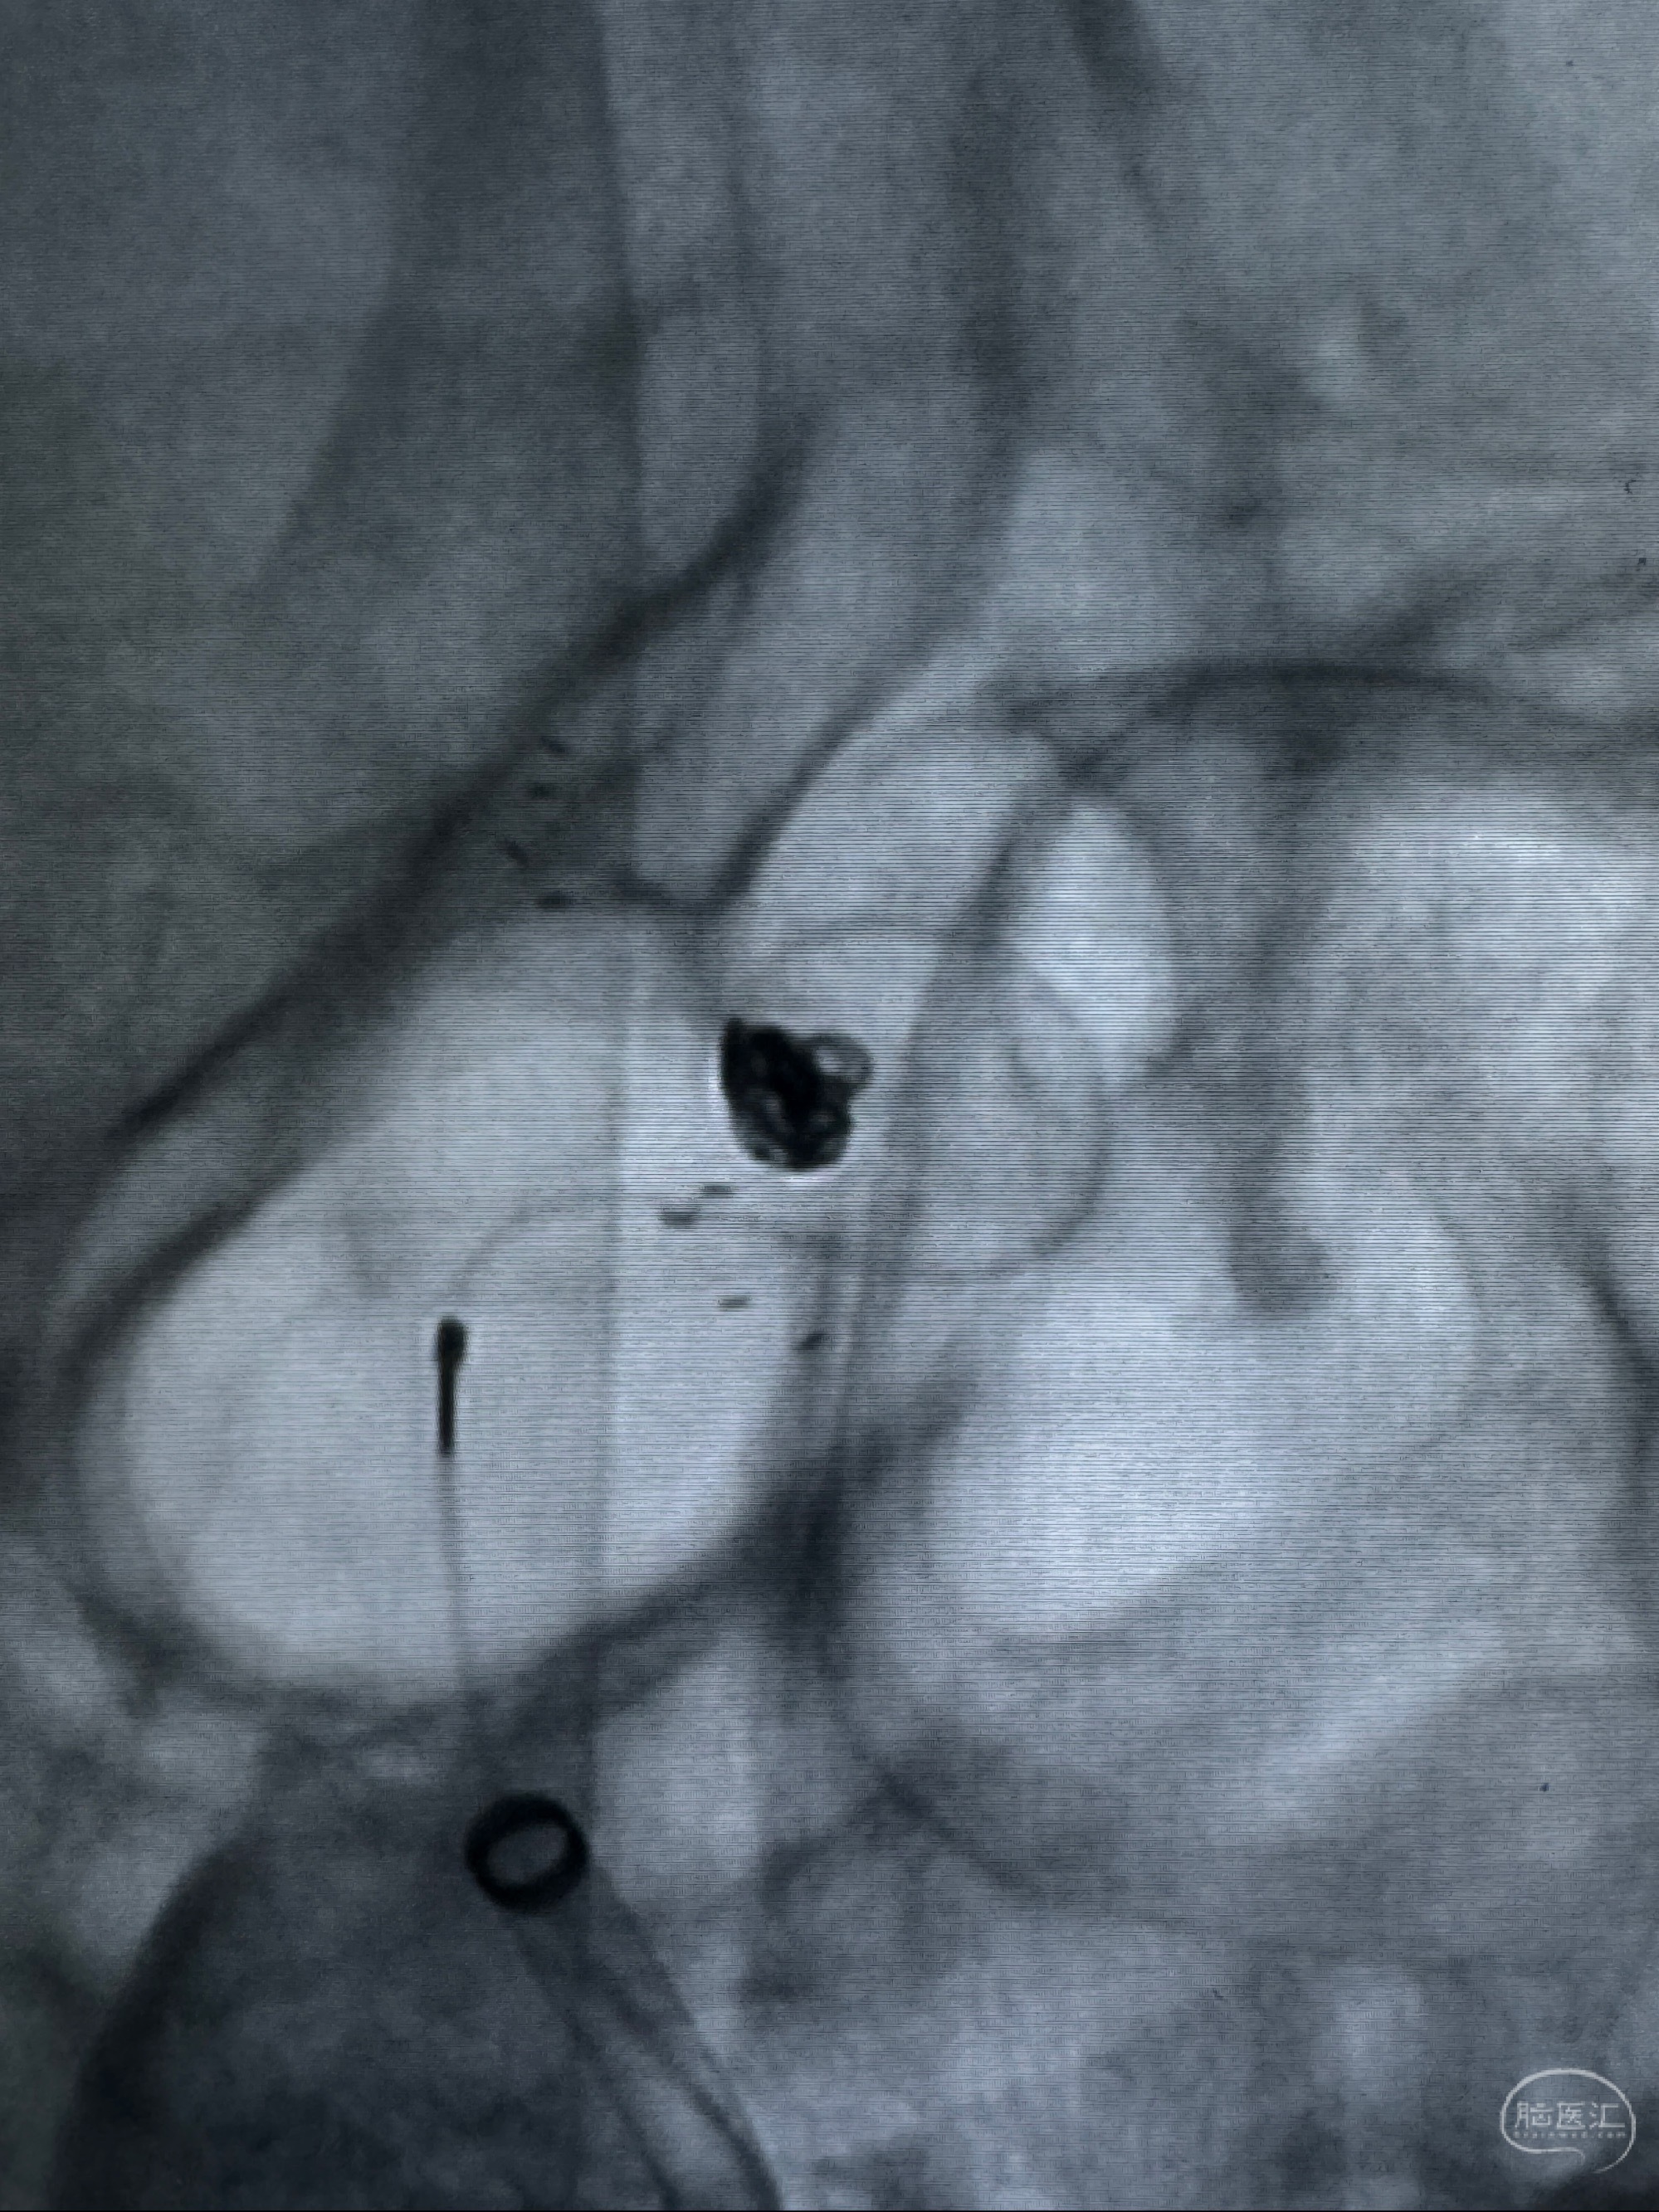

2023-11-13DSA:左侧颈内动脉眼动脉后壁动脉瘤

2023-11-29全麻下行NeuroformEZ4.5-20mm支架辅助栓塞